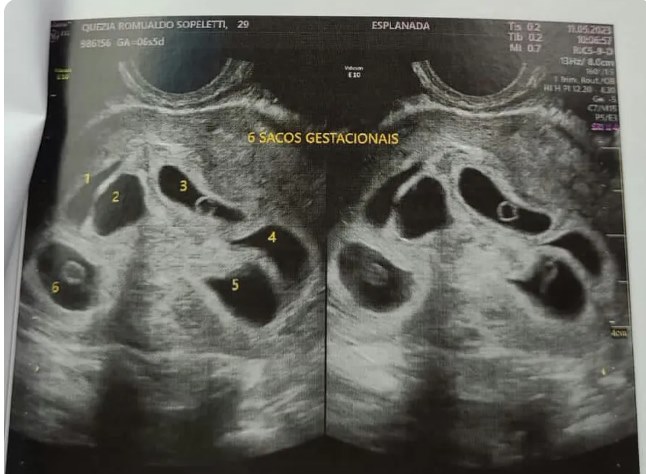

Dois dias antes do Dia das Mães deste ano, Quezia Romualdo, de 29 anos, foi ao médico fazer o primeiro ultrassom de sua segunda gestação. O objetivo era saber se estava correndo tudo bem com a gravidez. Mas a empolgação logo se transformou em surpresa quando, durante o exame, a médica foi mostrando que, na verdade, não era apenas um bebê que Quezia carregava no útero. A médica começou a contar. Primeiro, perceberam que eram três bebês. Depois, a contagem só foi aumentando: 4, 5, até chegar a 6!

Em entrevista ao g1, a radiologista Andréa Raposo, que fez a ultrassom em Quezia na quinta-feira (11), confirmou a gravidez dos sêxtuplos.

“Quando começou o exame, eu já tinha visto uns três ali. Mas aí a médica falou: ‘calma que tem mais’. Aí ela começou a contar: 1, 2, 3, 4, 5, 6. Na hora que ela falou seis eu até passei um pouco mal. Saí da sala, depois voltei e perguntei se ela tinha certeza. Depois a médica colocou pra gente ouvir todos os 6 coraçõezinhos , um por um”, relatou Magdiel.

“No primeiro momento é um choque para todo mundo. A gente vai vendo e durante o exame o número de bebês só foi aumentando. É quatro, é cinco, é seis”, disse Andréa.